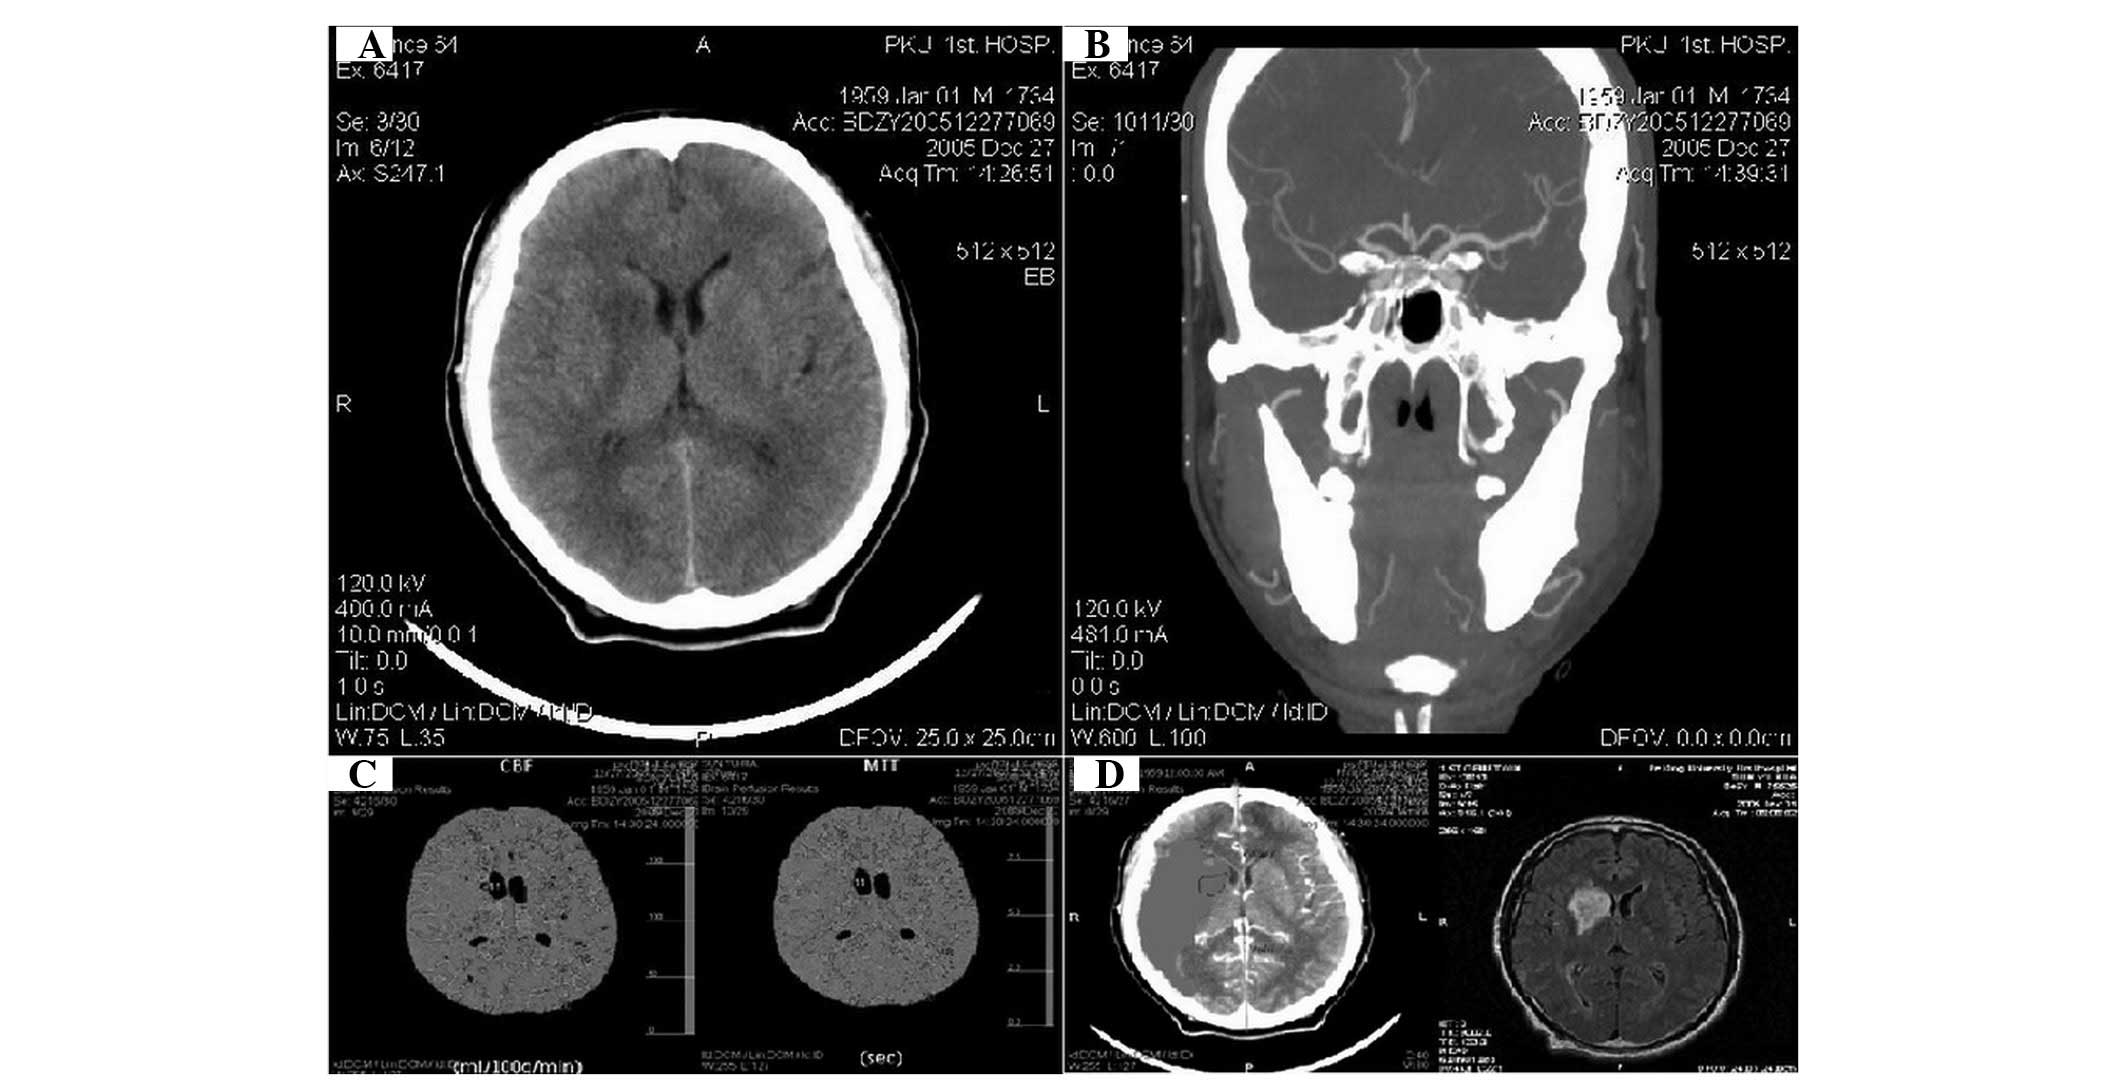

Figure 1.

Case 1, male, 46 years old, with mixed aphasia combined with left limb weakness for 5 h. The patient was admitted to hospital and presented no changes in consciousness. (A) A plain computed tomography (CT) scan revealed that cerebral infarction occurred in the right basal ganglia, corona radiata and semiovale center, right temporal lobe and parietal lobe. (B) CT angiography (CTA) revealed that the first portion of the right middle cerebral artery was in severe stenosis. (C) Cerebral blood flow (CBF) in the area of the right brain lesion was significantly reduced; the CBF ratio was <0.2, indicating irreversible ischemia. The CBF ratio around the lesion core was >0.2, indicating the ischemic penumbra. The mean transit time (MTT) of the right brain lesions was extended. (D) An infarct size of infarct area was identified by magnetic resonance (MR)-weighted imaging at <7 days.